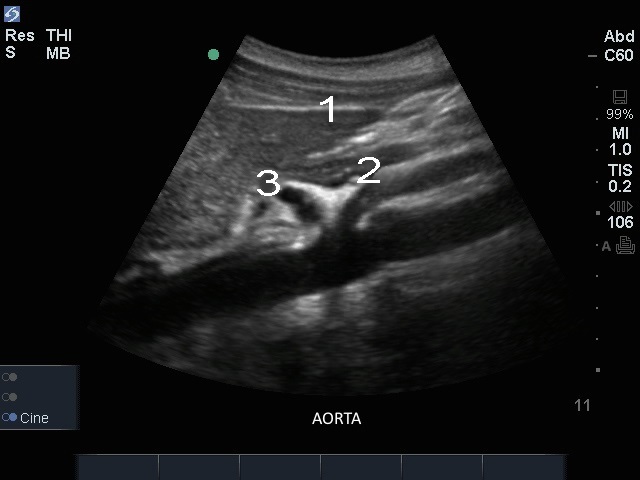

Edge: Sagital de la aorta

Hígado

CA

Arteria mesentérica superior (AMS)